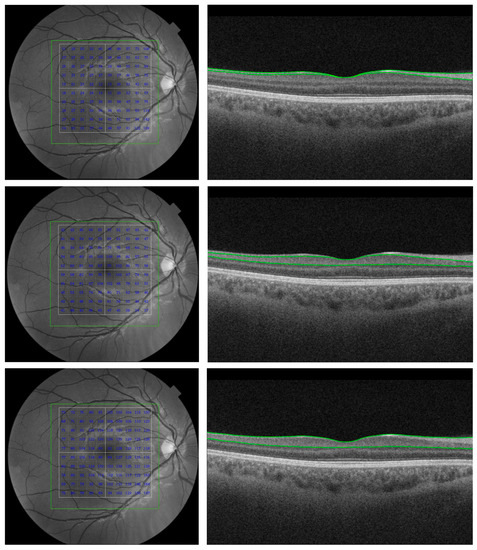

- Loh, E.H.-T.; Ong, Y.-T.; Venketasubramanian, N.; Hilal, S.; Thet, N.; Wong, T.Y.; Chen, C.P.L.; Cheung, C.Y.-L. Repeatability and reproducibility of retinal neuronal and axonal measures on spectral-domain optical coherence tomography in patients with cognitive impairment. Front. Neurol. 2017, 8, 359. [Google Scholar] [CrossRef] [PubMed]

- Snyder, P.J.; Johnson, L.N.; Lim, Y.Y.; Santos, C.Y.; Alber, J.; Maruff, P.; Fernández, B. Nonvascular retinal imaging markers of preclinical Alzheimer’s disease. Alzheimers Dement. 2016, 4, 169–178. [Google Scholar] [CrossRef] [PubMed]